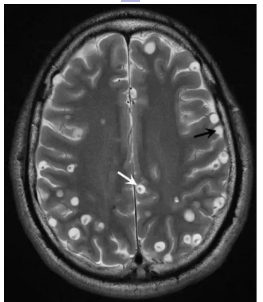

鲁先生因左下肢抽搐1周

到普洱市中心医院

影像学检查显示如下:

上图是不是没看懂?

简单来说

就是鲁先生诊断为脑囊虫病